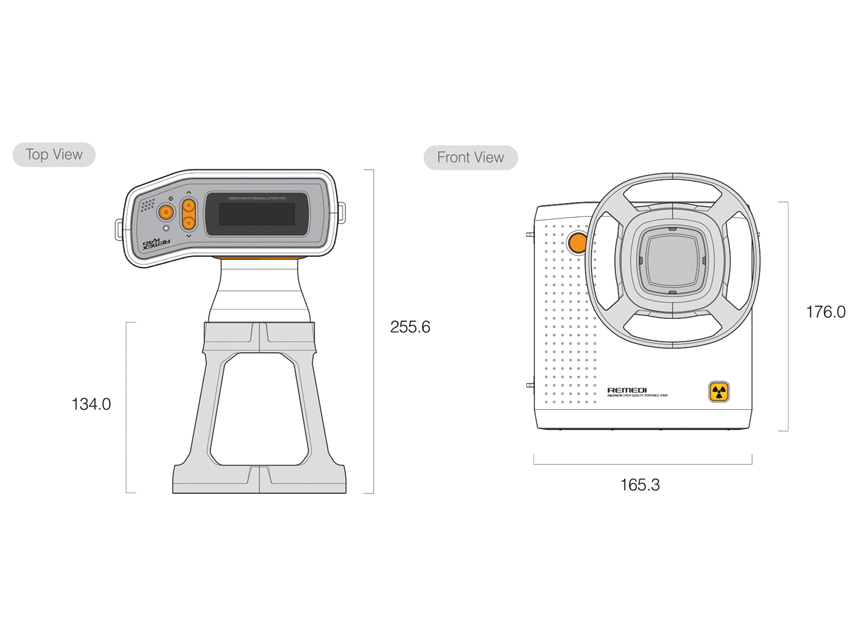

- Dimensions compactes : 165,3 x 176 x 255,6 mm, poids léger de 2,4 kg.